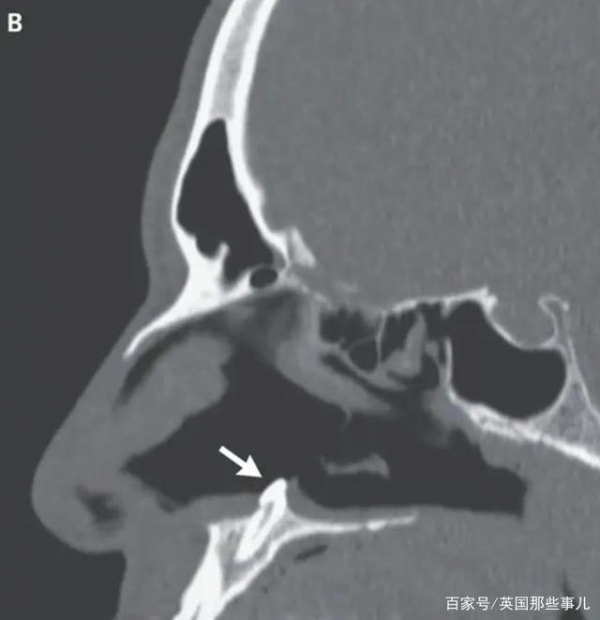

继续检查时,医生们在鼻中隔后方发现一个“坚硬、不会压痛、白色的异物”,仔细辨认之后,他们确认这是一颗牙齿。这颗牙齿约有15毫米长,谁都不知道它为啥会长在鼻孔里,A的面部没有受过任何创伤,也看不出任何异常,医生找不到病因。

A的这种情况叫做鼻腔异位齿,是非常罕见的现象,病因目前也无法确认,2019年的一项研究显示,鼻腔异位齿的发病几率只有0.1%-1%,因为大多数异位齿都长在牙龈里,也就是颌骨上。搞清楚病灶之后,医生们给A进行了口腔和耳鼻喉联合手术,成功将右鼻孔中的牙齿取出。